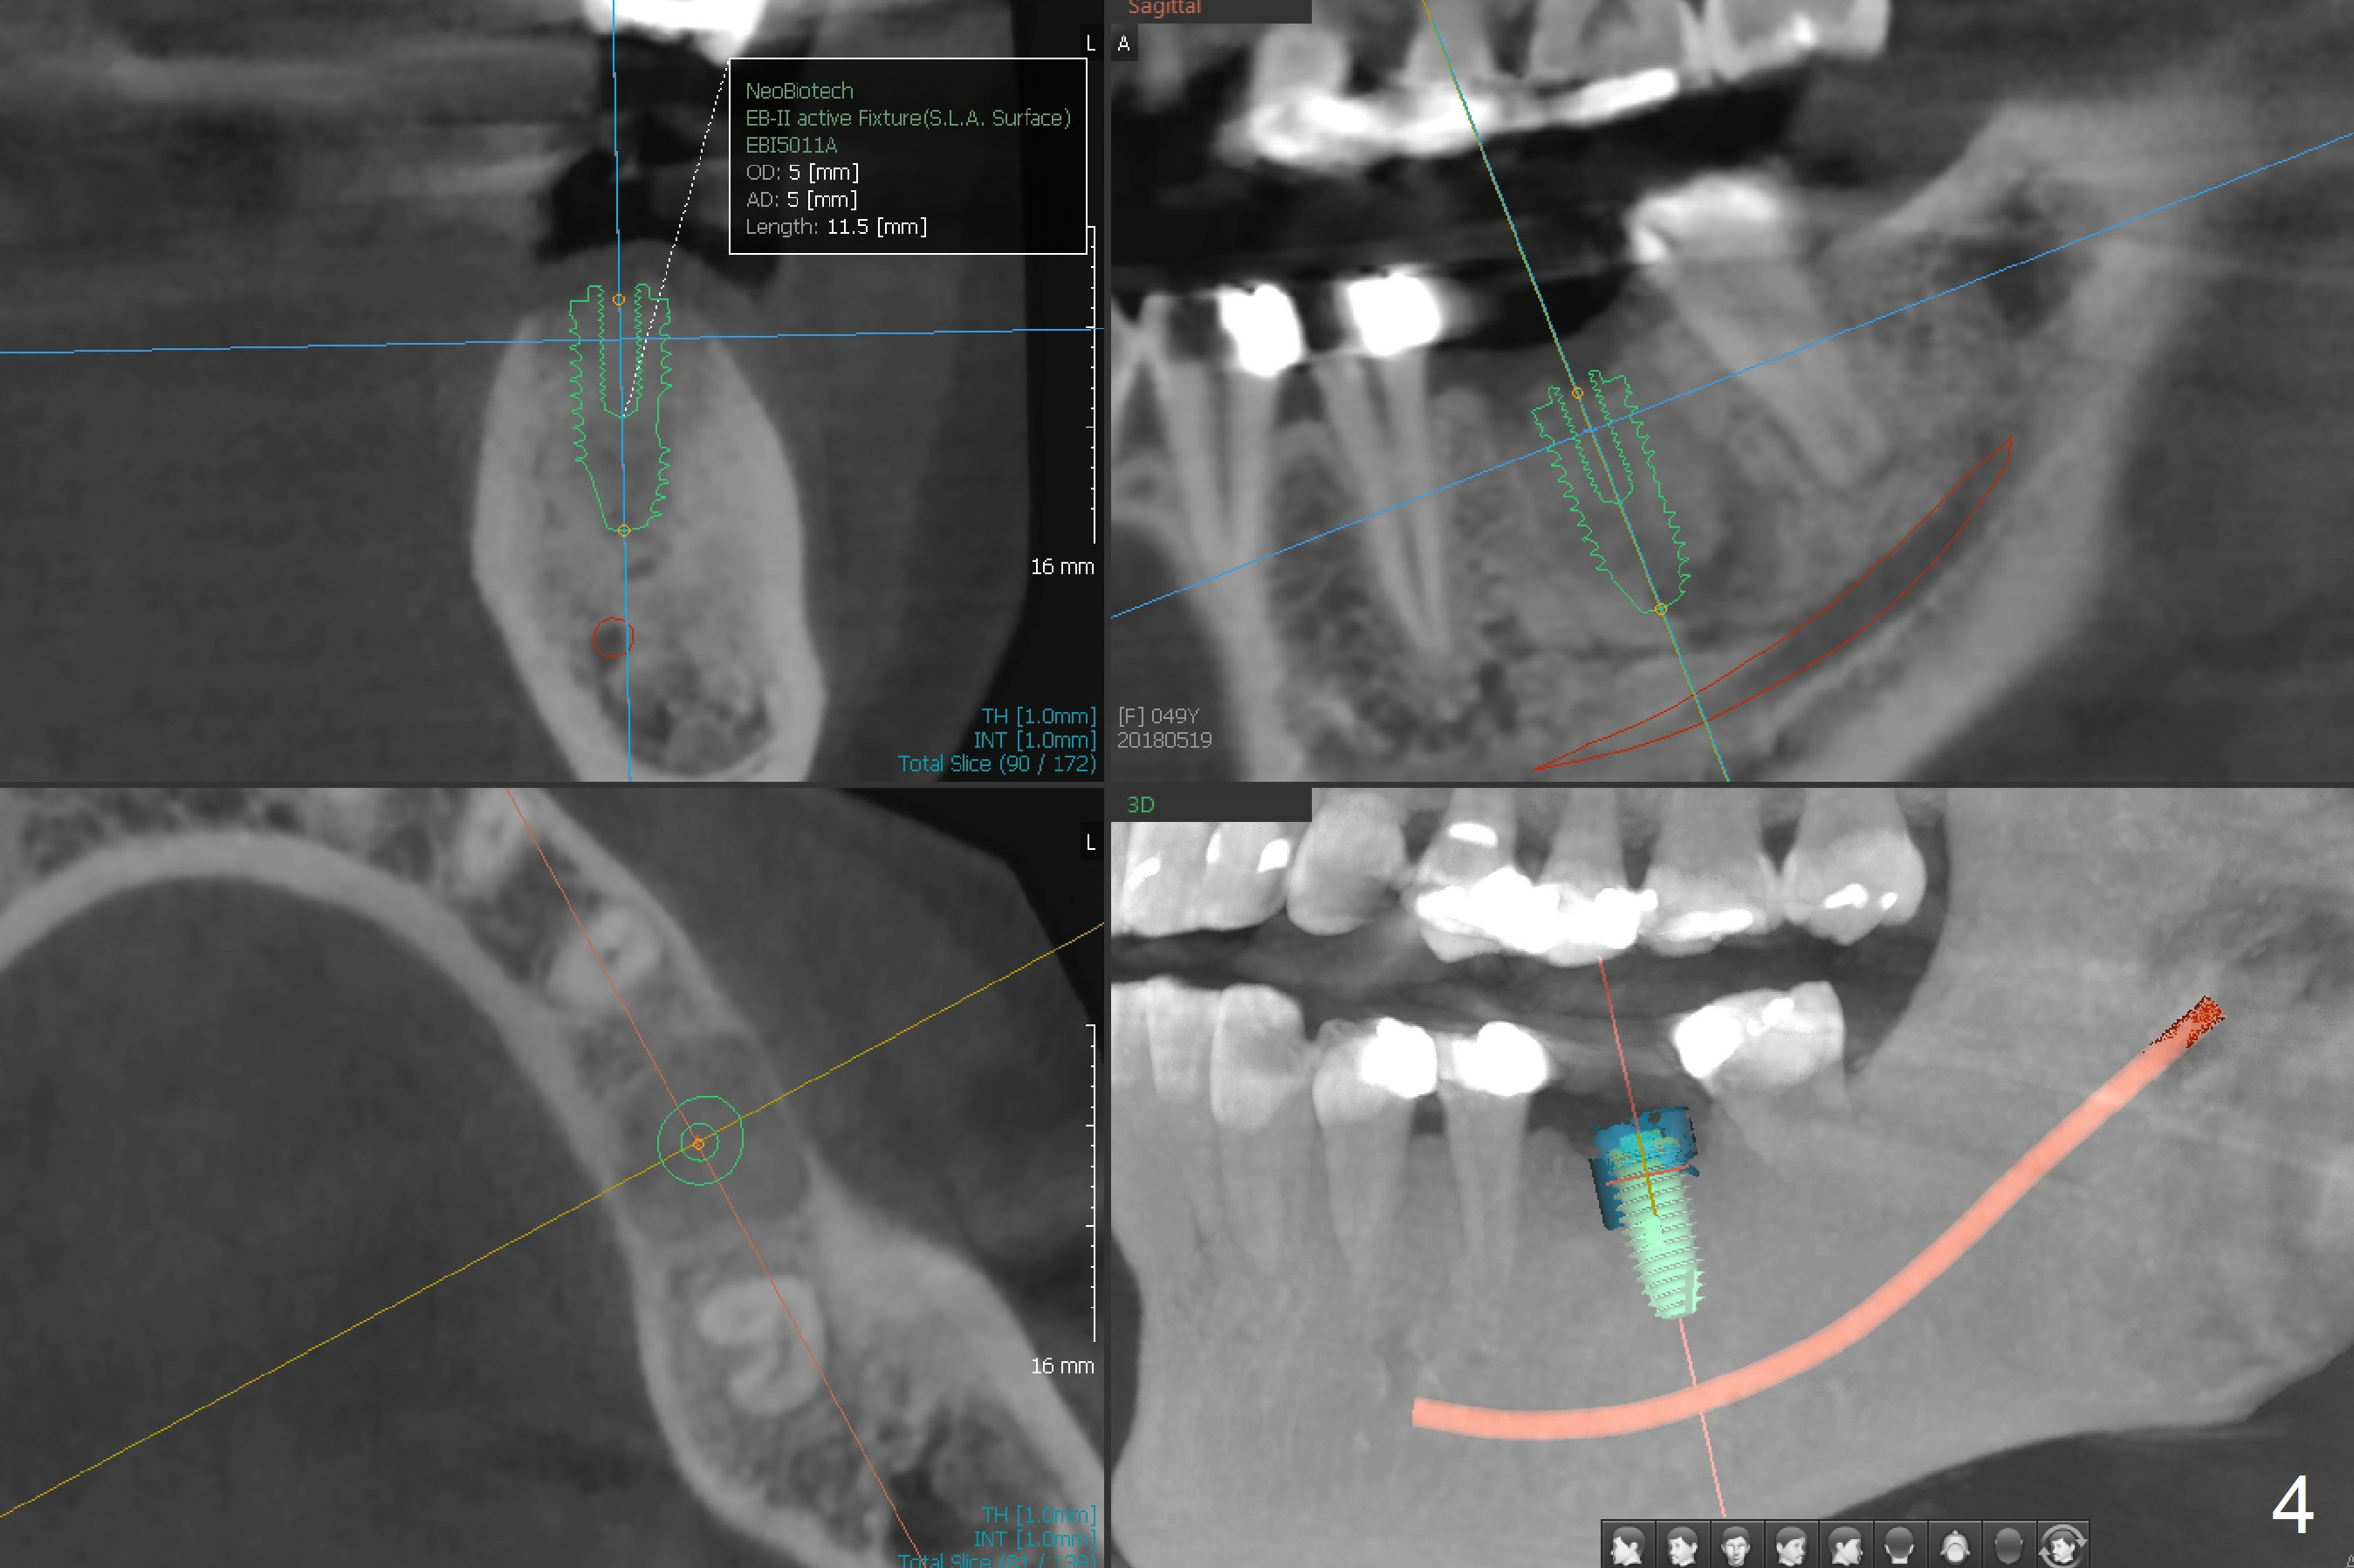

A 53-year-old woman has discomfort at #19 4-5 years post RCT (Fig.1 (*: PARL), 1 year before extraction). She returns for implant placement 4 months post socket preservation in other office (Fig.2 *). The socket appears to have healed with dense bone formation (average 1160 units, Fig.3). A 5x11.5 mm implant will be placed with guide (Fig.4). Will composite at #20 MOL (Fig.2 arrowhead) and PVS impression after CBCT affect surgical guide fabrication accuracy? Or the composite should be done after guided surgery?